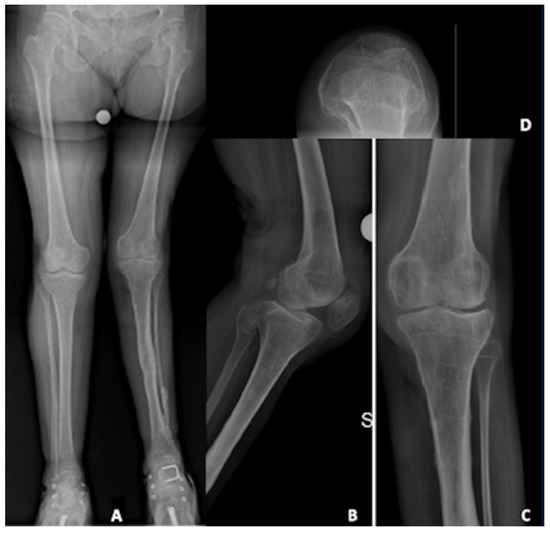

3.3. Clinical Case: Primary TKA in Poliomyelitis

A 58-year-old female patient suffered of poliomyelitis in her childhood, with subsequent left lower limb muscular deficiency. She came to our attention complaining about a left knee pain. The patient was a small lady, 150 cm in height, 47 kg in weight, with a Body mass Index (BMI) of 21 kg/m2. Due to poliomyelitis, she underwent three different surgeries for lower limb elongation and a hindfoot fusion. She was diagnosed with left knee osteoarthritis, and, after failure of initial conservative treatment, she was recommended for TKA. Figure 1 shows pre-operative X-rays.

At the clinical evaluation, the patient was able to fully extend the knee, with a flexion limited to 100° due to pain. There was a partially reducible valgus deformity, with severe lower limb muscular deficiency, a positive valgus stress and recurvatum and valgus thrust during gait. Furthermore, there was a mild-to-moderate extension lag mainly due to quadricep muscle deficiency.

Figure 1. Pre-operative X-rays evaluation: (A) long-leg weight-bearing view; (B) lateral view; (C) antero-posterior view; (D) patellar view.